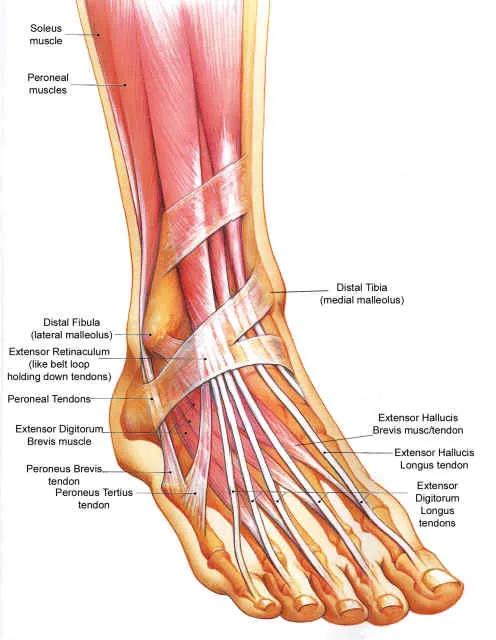

仔细研究一下,这个位置属于足弓的一部分,肌腱附着比较多,挺重要的